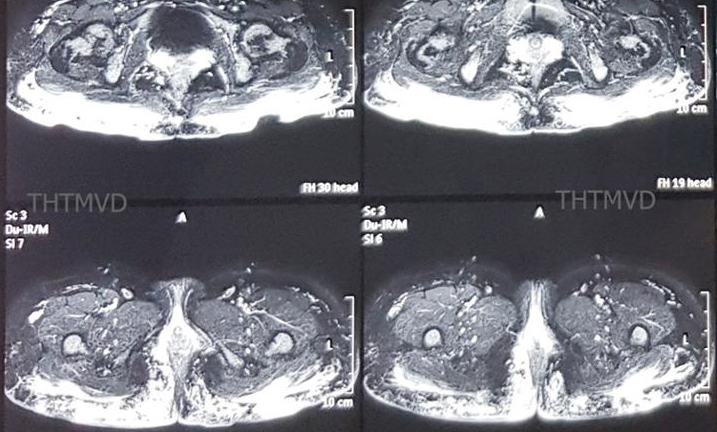

Tiêm mỡ nhân tạo để làm đẹp vòng 3 ở spa, người phụ nữ đau đớn khi vùng này bị hoại tử, phải điều trị hơn 6 tháng ở Bệnh viện Hữu nghị Việt Đức (Hà Nội) mới ổn định.